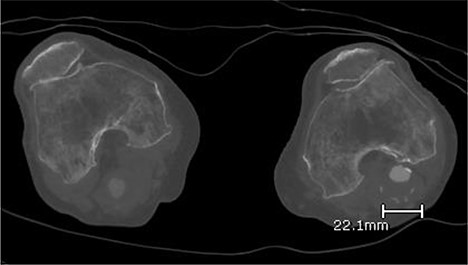

A 92-year-old female, independent from home, presented after multiple falls due to a four-month history of left foot drop. The foot drop had gradually worsened to the point that there was complete paralysis of ankle dorsiflexion and was associated with significant oedema of the foot. On examination, there was a large pulsatile mass in the popliteal fossa bilaterally. All peripheral pulses were palpable without any signs of ischemia. The most striking examination finding was complete paralysis of left ankle dorsiflexion with 0 out of 5 power. Ultrasound revealed that there were (Fig 1) bilateral popliteal artery aneurysms, which was larger on the left, causing displacement and impingement of the common peroneal nerve at the knee crease (Fig 2). Further computed tomography angiogram demonstrated an unruptured left PAA measuring 22 × 21 mm in maximal dimension over a distance of 24 mm (Fig 3). Intraluminal thrombus was also noted with 60% luminal stenosis. Distally, the arteries were heavily calcified with two-vessel runoff at the ankle. An emergency endovascular repair of the left PAA was performed by using 8 mm × 15 cm and 7 mm × 10 cm Gore Viabahn stents (Fig 4). The stents were deployed after a balloon-angioplasty and adequate decompression of the aneurysm was achieved. The postoperative period was uneventful, and patient’s pre-existing aspirin was continued. The leg and foot oedema improved rapidly over the subsequent few days. At follow-up in 12 weeks, the patient showed some return of motor function of the ankle and was walking with ankle splint. Her left leg remained well perfused with palpable pulses.

Ultrasound image of left popliteal artery aneurysm, causing displacement and impingement of the common peroneal nerve (indicated by the white arrow).